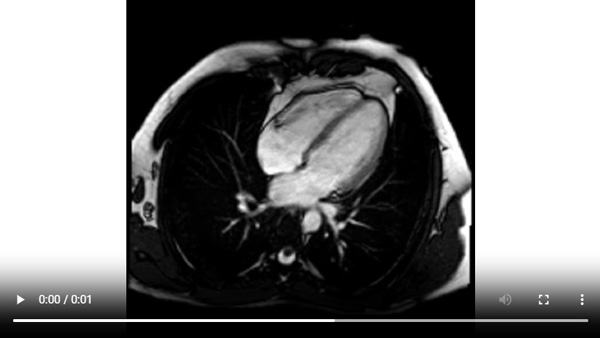

Figure 1A : Séquence Ciné-IRM - Coupes petit-axe basal

Figure 1B : Séquence Ciné-IRM - Coupes petit-axe médian

Figure 1C : Séquence Ciné-IRM - Coupes petit-axe apical

Figure 1D : Séquence Ciné-IRM - Coupes 2-cavités

Figure 1E : Séquence Ciné-IRM - Coupes 3-cavités

Figure 1F : Séquence Ciné-IRM - Coupes 4-cavités

Visualisation d’un rehaussement myocardique systolique à prédominance sous-épicardique sur les cinés long-axe (2 cavités et 3 cavités) acquises après injection de gadolinium. C’est un signe assez évocateur d’œdème myocardique, qui est souvent retrouvé en cas de myocardite aiguë.